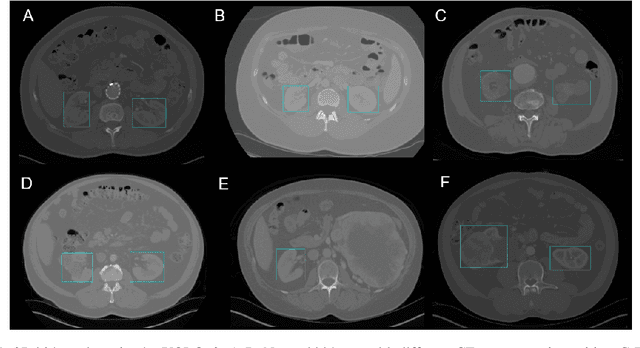

Abstract:Organ localization can be challenging considering the heterogeneity of medical images and the biological diversity from one individual to another. The contribution of this paper is to overview the performance of the object detection model, YOLOv3, on kidney localization in 2D and in 3D from CT scans. The model obtained a 0.851 Dice score in 2D and 0.742 in 3D. The SSD, a similar state-of-the-art object detection model, showed similar scores on the test set. YOLOv3 and SSD demonstrated the ability to detect kidneys on a wide variety of CT scans including patients suffering from different renal conditions.